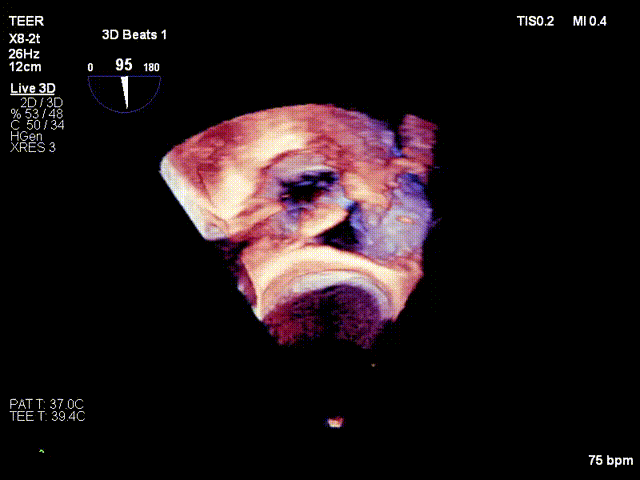

Surgical Procedure

After the patient was placed under general anesthesia, the jugular vein was punctured intraoperatively to establish surgical access. An 18Fr delivery sheath was advanced along a stiff guidewire to the mid-inferior right atrium, and the delivery system was introduced under ultrasound guidance. A 12T K-Clip® device was implanted at the posteroseptal commissure and another 12T K-Clip® device at the anteroposterior commissure respectively. The angle between the device and the annulus plane was adjusted through catheter deflection and rotation to direct the tip of the clip device to the target position. Under ultrasound MPR mode, the anchoring screw was deployed into the annulus. After confirming stable traction, the clamping arms were opened and apposed to the annulus, followed by retraction of the anchoring component to close the clamping arms for annuloplasty. The surgical effect was evaluated as satisfactory, and the clip components were then released.

Deployment of the anchoring component under the MPR view

Opening the clamping arms, adjusting the orientation and apposing to the annulus

Closing the clip

Efficacy evaluation after implantation of the first clip